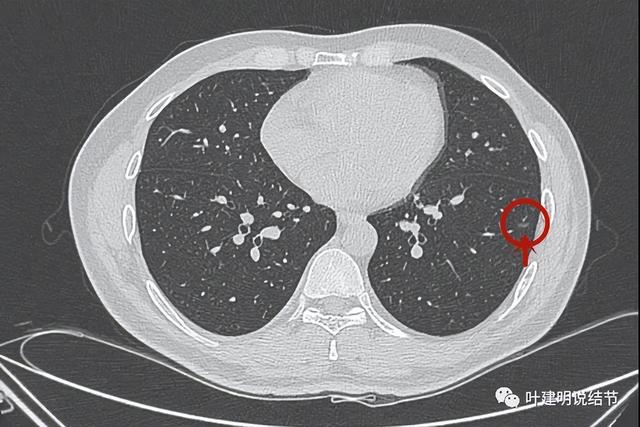

先来看最近检查的CT:

病灶出现

略显糊,中间有偏实性密度

这性密度呈点状,周围磨玻璃部分密度较低,整体轮廓较清

病灶微小,磨玻璃密度

整体还是显得偏糊了点

冠状位见有血管走向病灶(桔色箭头),病灶小又显糊

可见病灶变化甚微,或者根本就不明显。但它持续存在,是有血管穿行或进入的磨玻璃结节。

我的意见:

这个左下叶背段的病灶,从提供影像资料最早的2020年5月到2022年6月2年多的时间的没有明显进展,也无明显吸收好转。总体是磨玻璃结节,局部似密度略高,但太小了,说不上肯定是实性成分。总体轮廓较清,但瘤肺边界不是特别清晰,考虑慢性炎伴局灶肺泡上皮不典型增生可能性大些,至少目前风险很低的。如果继续半年或一年复查随访也可以(个人建议满3年可改年度复查,但稍倾向仍半年查一次)。不过鉴于位置非常好,在边上,如果单孔楔形切除只要切掉一点点肺组织,真有心理上压力,考虑切了也是可以的(个人倾向随访到有一定风险时再切更妥,因为怕随访中他处再有新发现结节,避免多次手术)。以上意见供参考!